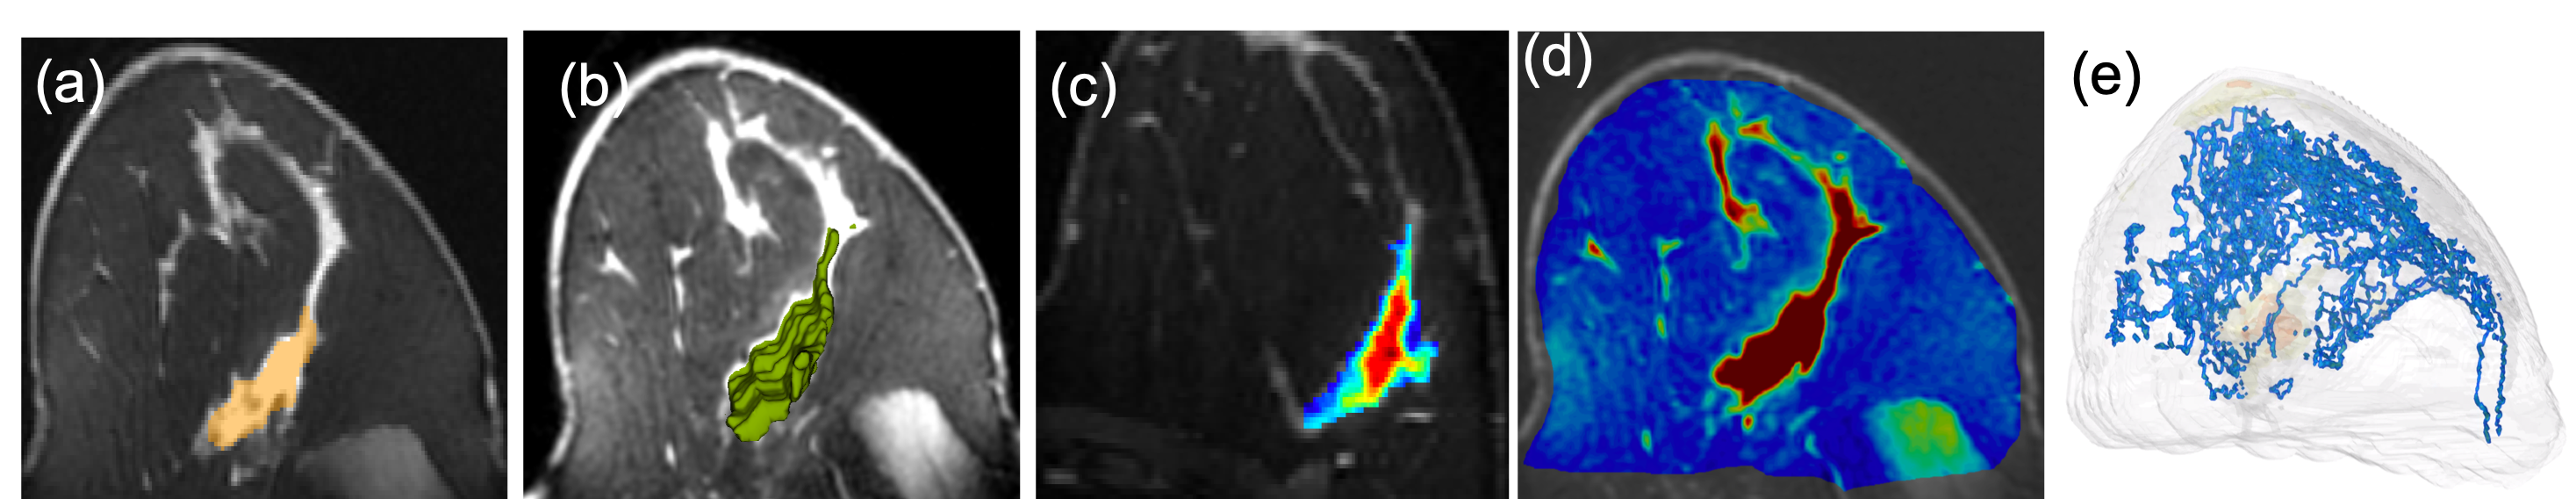

Refer to caption

Figure 1: An example MRI image (a) and different radiomics features such as (b) tumor 3D shape, (c) intratumoral texture (Haralick entropy), and (d) whole breast texture (Haralick energy). In (e), we show topological structures from TopoTxR, capturing the density of fibroglandular tissue.

We present a novel topological biomarker for breast DCE-MRI. Our method bridges the two extremes (hand-crafted imaging features vs. completely data-driven CNNs). The key idea is to direct the model’s attention to a much smaller set of voxels surrounding tissue structures with high biological relevance. This way, the deep convolutional network can be efficiently trained with limited MRI data. Meanwhile, the learning outcome has the potential of connecting to the biological cause manifested on the tissue structure topology. As shown in Figure 1, our topological descriptor (e) directly models the breast parenchymal tissue structures, whereas other features (b-d) do not.